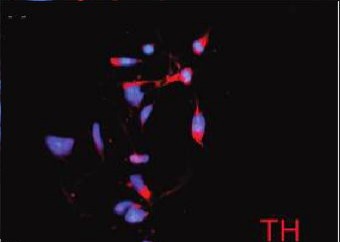

Image: TH (tyrosine hydroxylase, an excitatory neuronal marker) staining of STEMEZ(TM) hNP1 Human Neural Progenitors. doi:10.1089/ten.tea.2009.0155.

Markers to TH are important for studying its role in neurotransmission and how it is altered in disorders and diseases.